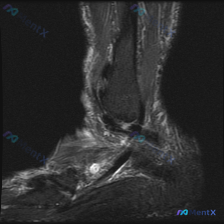

刚看到这个踝关节MRI的读片病例,整理了完整信息和分析思路分享给大家。 病例影像基础信息 这是踝关节矢状位T2加权压脂序列MRI,核心问题是图像中可见软组织液信号,我们来拆解分析: 影像学核心发现 1. 核心异常定位:距骨下方、跟骨上方的跗骨窦区域,存在明显信号异常 2. 跗骨窦内可见一个圆形/椭圆...